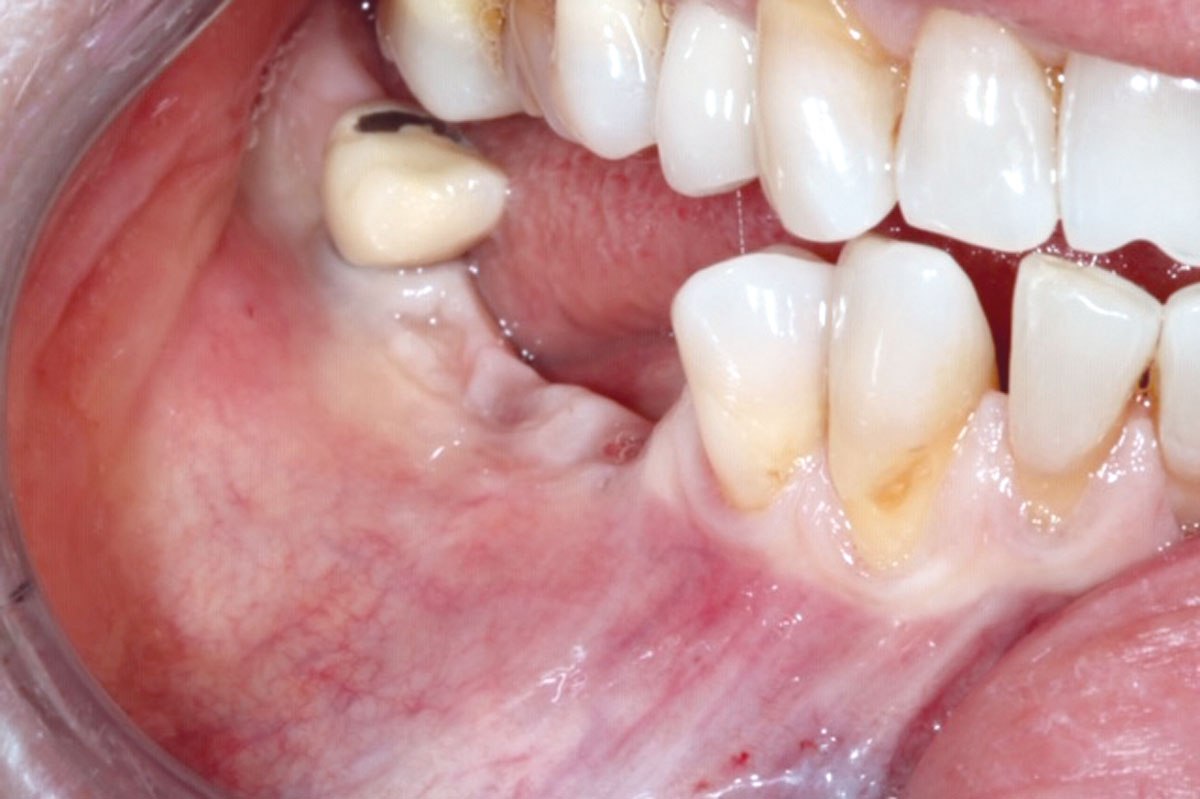

1/10 - Initial clinical situation.GBR with cerabone® and Jason® membrane DentalPro - Dr. A. Gargiulo

Initial clinical situation.